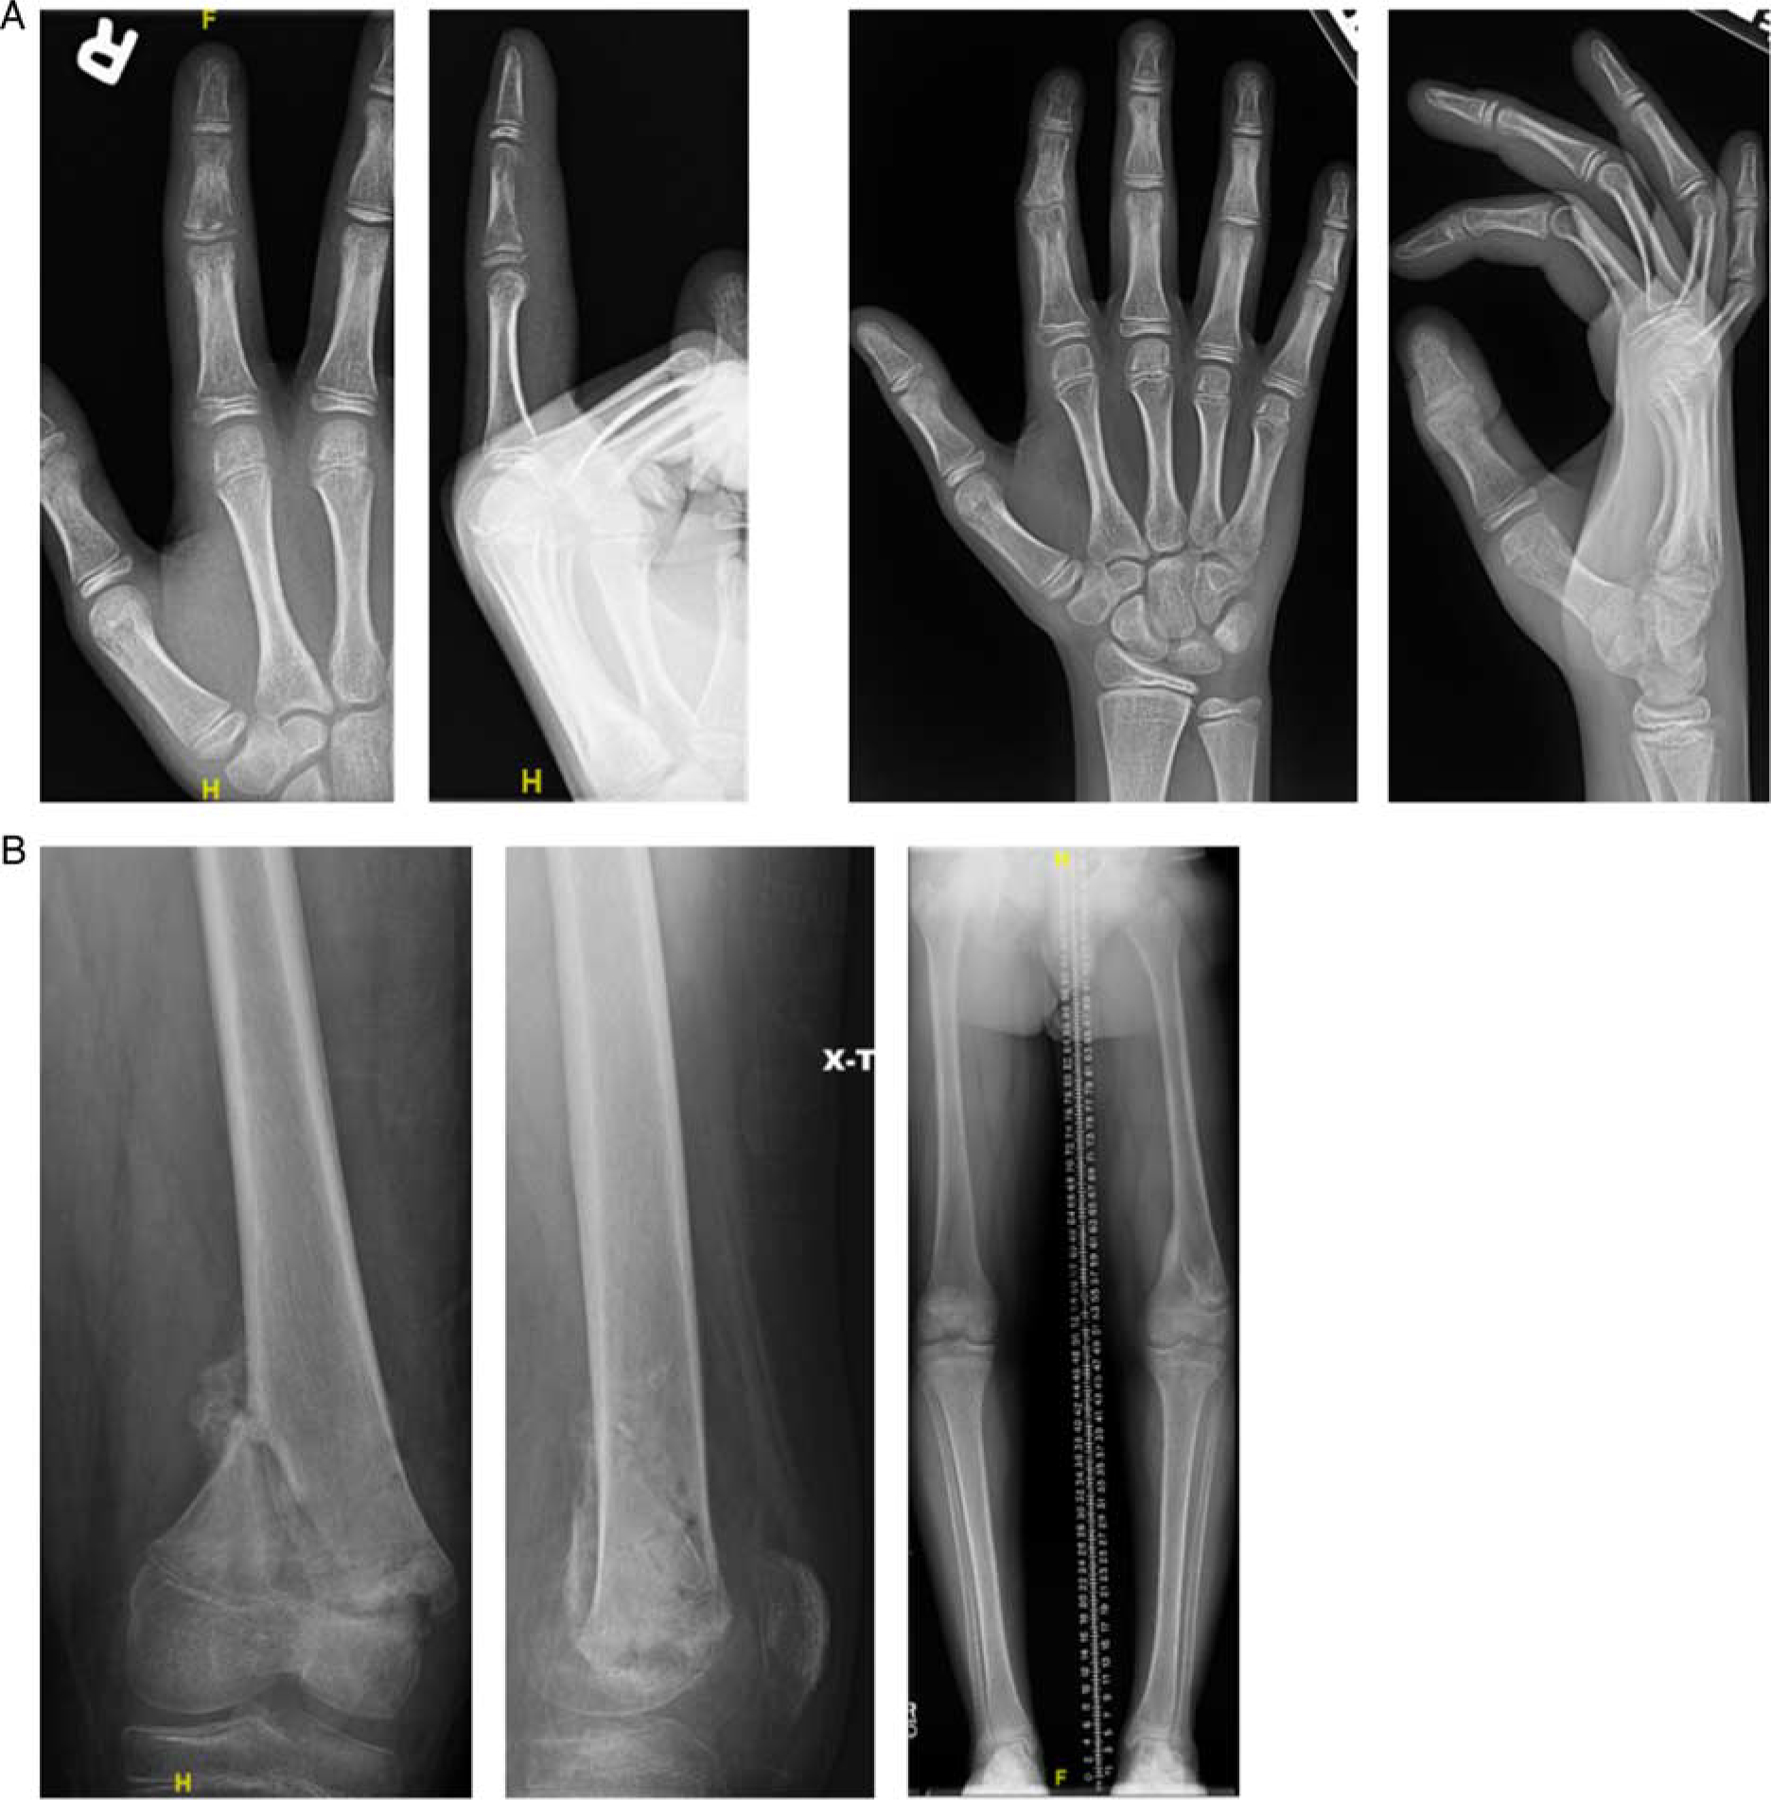

Of the 329 total screening radiographic series, a total of 287 (88%) routine radiographs were obtained, resulting in the detection of 2 (0.7%) negative sequelae. The number of routine radiographs required to detect 1 adverse outcome was 143 [95% confidence interval (CI): 36–573]. Routine monitoring was performed in 127 patients, resulting in number of patients required to monitor with routine radiographs to detect 1 adverse outcome of 64 (95% CI: 16–253). Routine radiographs detected 1 pathologic fracture and 1 instances of growth arrest (Fig. 1), which were detected on days 9 and 198 postdischarge, respectively.

FIGURE 1.

Negative sequelae of routine radiographs. A, Index finger osteomyelitis (left) and resultant ulnar deviation from middle phalanx growth arrest (right). B, Distal femoral osteomyelitis (left) and resultant leg length discrepancy (right).